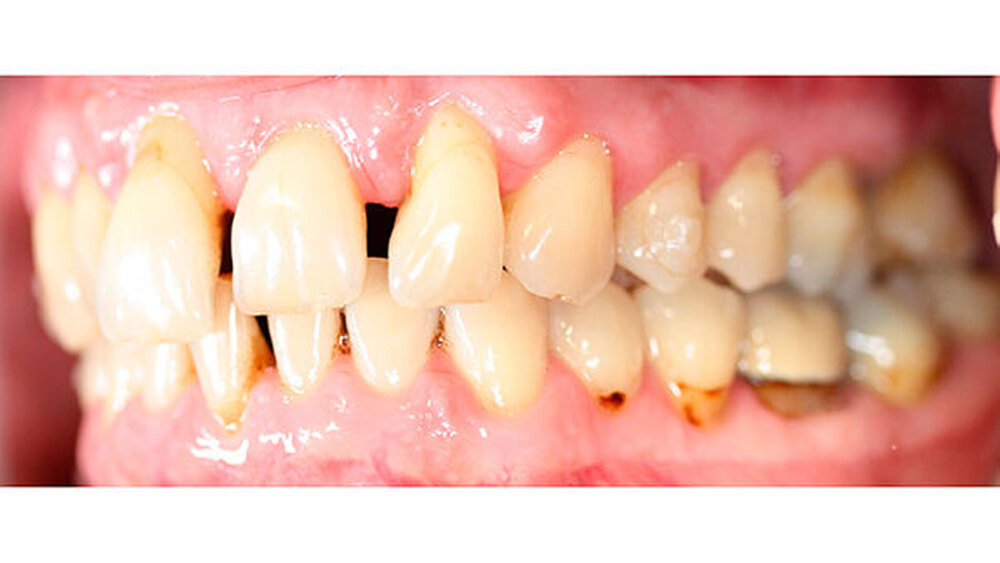

Intraoral zeigte sich ein bereits konservierend versorgtes permanentes Gebiss mit aktivem und inaktivem kariösen Geschehen. Große Anteile der Zahnhälse lagen nach Zahnfleischrückgang in Kombination mit Knocheneinbrüchen frei. Zahn 27 wurde bereits extrahiert.

Eine Beurteilung der parodontalen Situation an Zahn 11 offenbarte mesial und distal Sondierungstiefen von jeweils 6 mm.

Kieferorthopädisch imponierte beidseits eine neutrale Verzahnung bei einem tiefen Biss von 5 mm - bedingt durch die Verlängerung beider Frontzahngruppen. Besonders Zahn 11 zeigte eine erhebliche Verlängerung und Protrusion mit einer sagittalen Frontzahnstufe von 5 mm. Sowohl die Frontzähne im Ober- als auch im Unterkiefer wiesen eine lückige Beziehung zueinander auf (Abbildung 1).